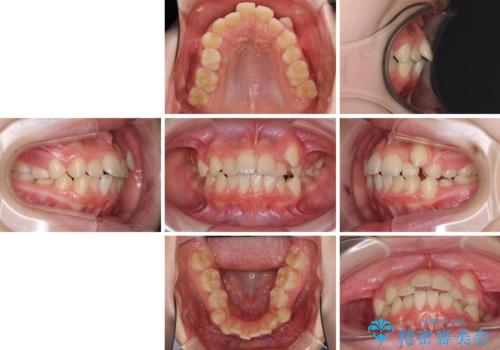

乳歯が残っている 目立たない装置での抜歯矯正

- 八重歯と乳歯が残っていることを気にして来院された患者様です。

乳歯が3歯残っており、下顎は左右ともに後続永久歯がない状態でした。

口元が突出しており、口が閉じにくかったため、乳歯を含め上下5歯を抜歯して矯正治療を行うこととしました。

下顎の乳歯は永久歯と比べて幅が大きいため、抜歯した場合のスペースが大きく、治療には長期間を要することが一般的です。

今回の患者様は中学生ということもあり、成人の患者様と比べ動きが速く、2年間で治療を終えることができました。